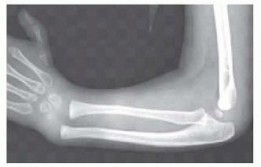

Radial Dysplasia Reconstruction DEFINITION Radial dysplasia represents a spectrum of longitudinal deficiency …